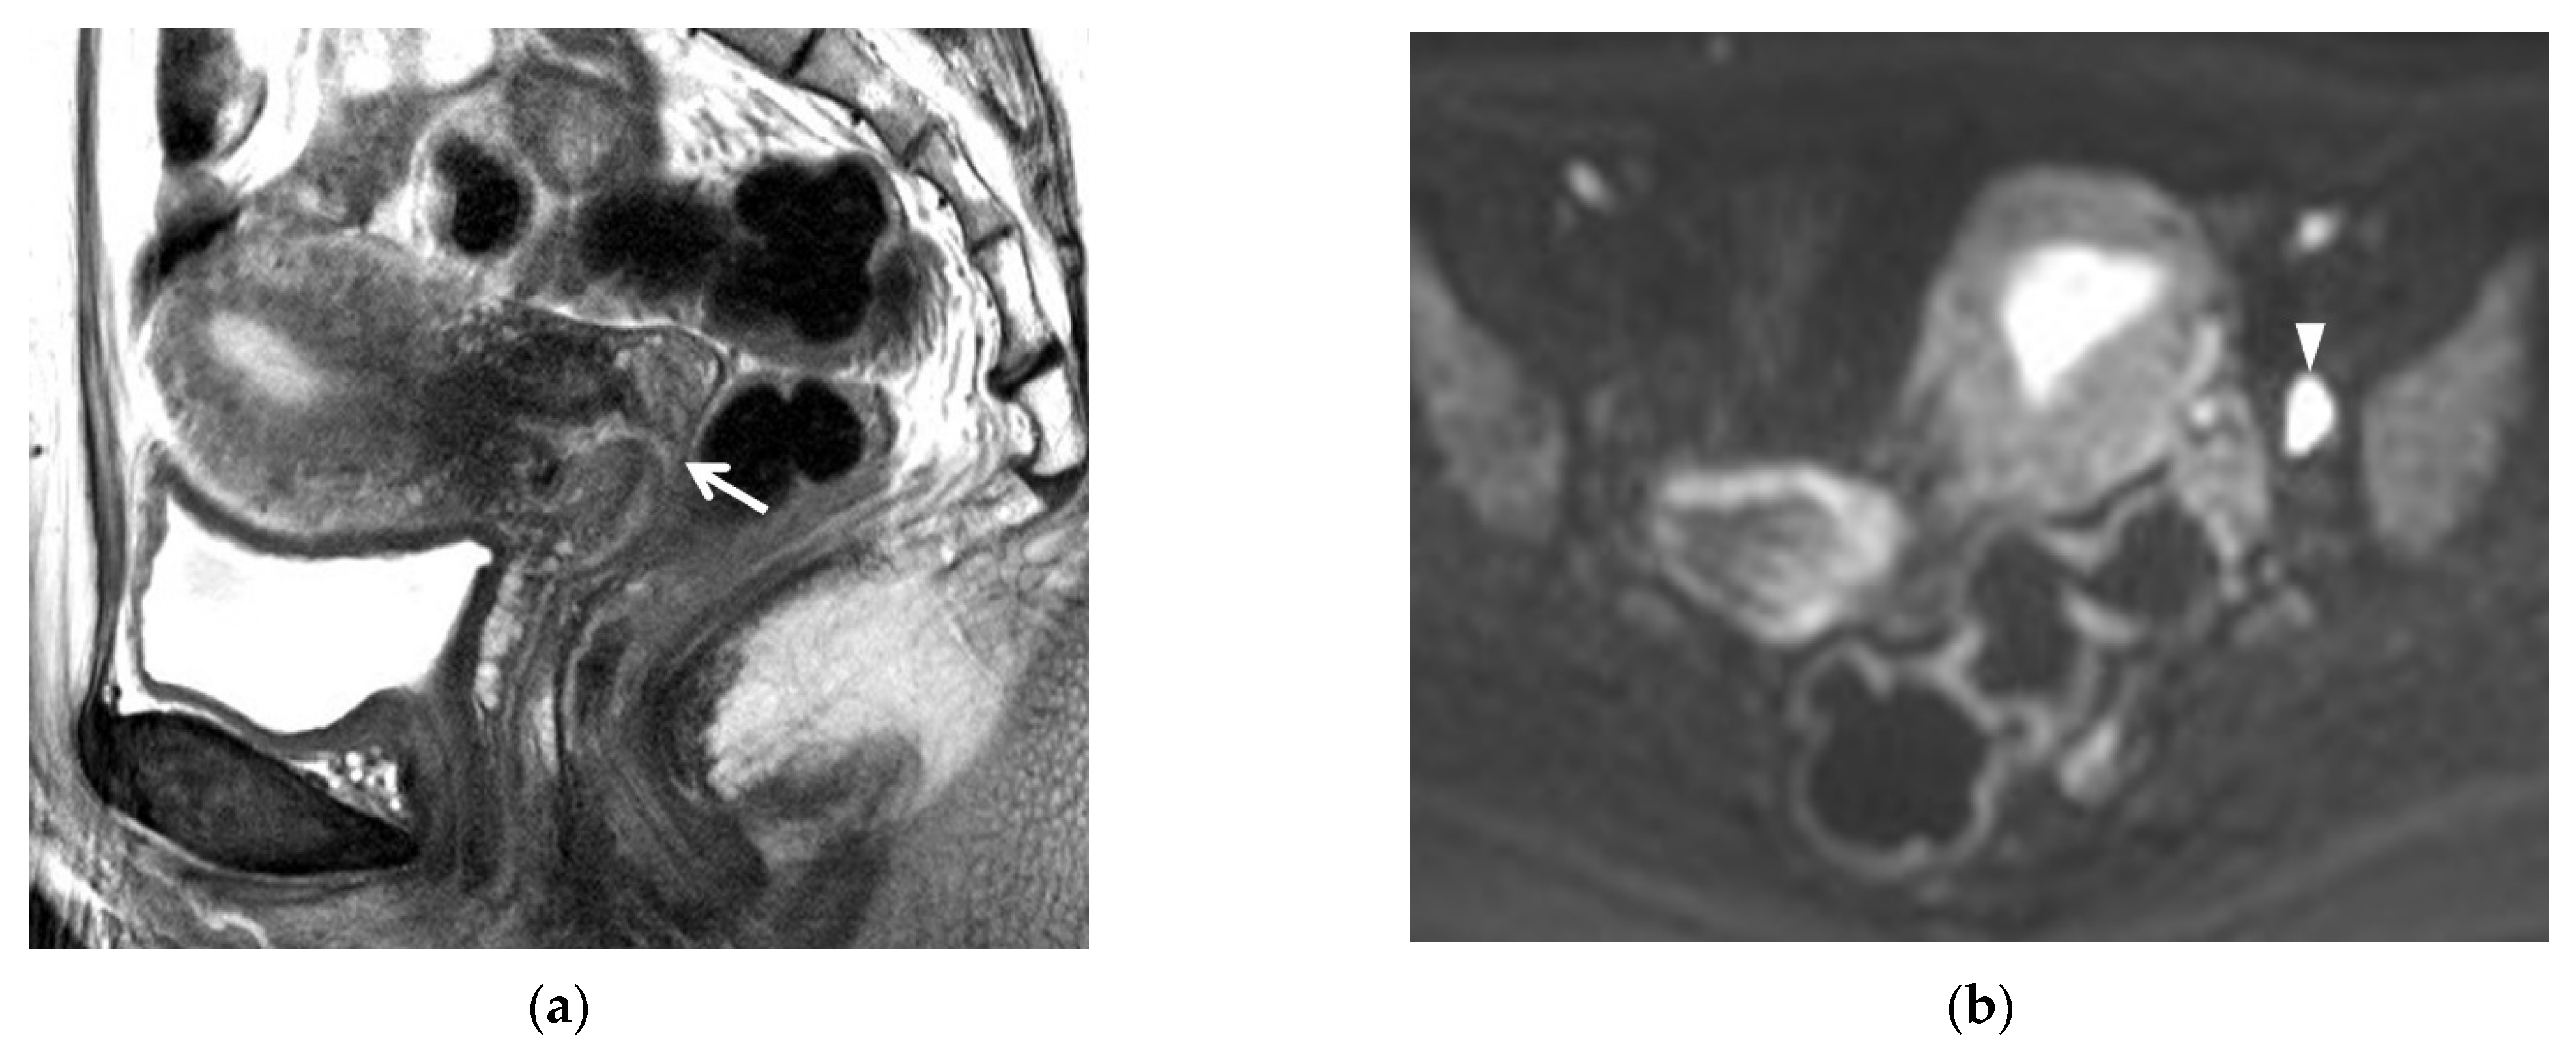

2.2. T2-Weighted Imaging (T2WI)

2.4. Diffusion-Weighted Imaging (DWI)